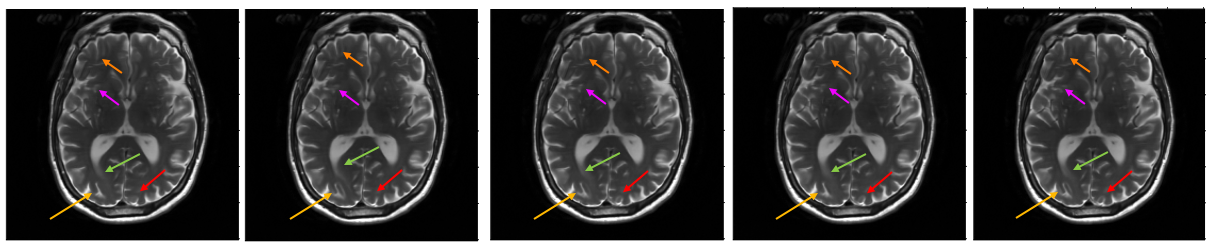

8.3 Performance comparison with SOTA diffusion solvers

Table 4 summarizes the quantitative results for a range of inverse problems, comparing ALPS with DAPS and DPS using PSNR and SSIM metrics. The MMSE estimates are obtained by computing the average of five different samples. The algorithms are tested on different slices. We also report the maximum-a-posteriori (MAP) estimate given by the multi-scale EBM which involves the following update rule (refer to Sec 3.6 in the main paper for more details):

The inverse is computed using conjugate gradient method. For random inpainting tasks, ALPS consistently outperforms DAPS across different corruption levels (). The performance gap widens as the noise variance becomes less severe. At high noise levels, the performances are closer. In the less challenging D setting, DPS is observed to offer a slightly higher PSNR than ALPS and DAPS, but as the complexity increases (e.g., D and D), ALPS demonstrates clear superiority. This trend indicates that ALPS scales better with problem complexity, likely due to its ability to exploit forward model structure during sampling. Table 4 also shows the MAP estimate, which does not require averaging over multiple posterior consistent samples. From the table, it can be observed that MAP performs better than MMSE estimates for the inpainting tasks at all the corruption levels.

While the table focuses on reconstruction quality, it is important to note that ALPS achieves these results with fewer function evaluations compared to DAPS. This efficiency stems from ALPS’s smoother trajectory from initialization to posterior, reducing the need for excessive annealing steps and iterations. Fig. 9 shows the MAP estimate and posterior sample generated via ALPS algorithm for different inverse problem. We also show the MRI reconstructions at different accelerations in Fig. 10. Fig. 11 shows the three different estimates that are given by the EBM: MAP, MMSE, and the uncertainty estimates for three different accelerations. One can observe that as the acceleration increases, the uncertainty of the reconstruction also increases. We also report the average NLPr and negative log-posterior (NLPo) values of the generated samples across different accelerations in Table 5. One can observe that as the acceleration increases, the mean NLPr and mean NLPo values decrease. This occurs because higher acceleration leads to more severe undersampling, making the reconstruction problem increasingly ill-posed. In such settings, the ALPS algorithm relies more heavily on the energy model. As a result, the algorithm outputs reconstructions with lower prior energies, and the posterior energies follow the same trend due to the reduced influence of the negative log-likelihood term.